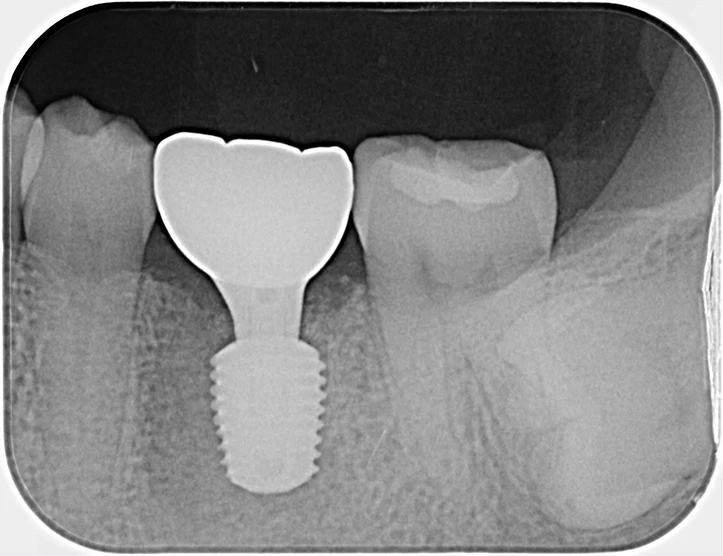

40代、女性、左下噛むと痛いこと主訴に来院され、インプラント治療を行いました。

| 診断結果 | 左下6番歯根破折 |

| 治療内容 | 抜歯即時インプラント |

| 治療期間 | 8週間 |

| 治療費用 | ¥539,000(税込) |